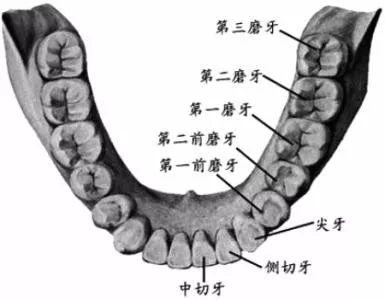

智齒,學(xué)名三大臼(jiù)齒,又叫做第三磨牙。

雖然叫做智齒,但其實(shí)和智商毫無(wú)關(guān)系...只是一般在 18 歲后長(zhǎng)出來(lái),正處于人類智力發(fā)育的鼎盛期而得名(小時(shí)候看鄭淵潔的《智齒》,一直對(duì)自己沒(méi)有長(zhǎng)智齒而耿耿于懷,現(xiàn)在,悔之晚矣...)。

人類在進(jìn)化過(guò)程中,進(jìn)食的食物是越來(lái)越精細(xì),頜骨(就是你的下巴)越來(lái)越短,但牙齒不會(huì)減少,有的牙齒就沒(méi)有空間長(zhǎng)出來(lái)。嚴(yán)肅的推斷出「智齒長(zhǎng)不好,說(shuō)明你臉小」(強(qiáng)行安慰一波長(zhǎng)阻生智齒的人)...